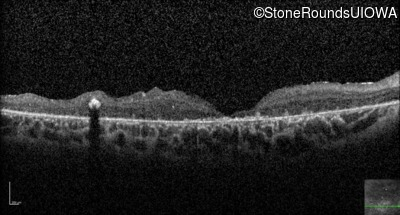

Optical Coherence Tomography - Right - 20/400 sc

Exemplar / OCT Stack